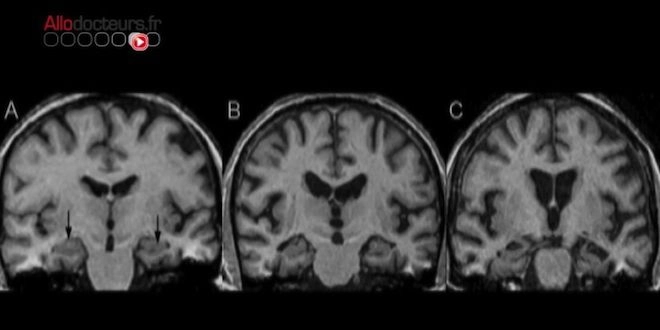

Chez la souris, les chercheurs ont provoqué une infection du cerveau par une bactérie du nom de Salmonella Typhimurium. L'organisme du rongeur n'a pas tardé à réagir : des dépôts de bêta-amyloïde se sont rapidement formés, très proches des lieux de prolifération de la bactérie. Les résultats évoquent la possibilité, intrigante, que le peptide puisse jouer un rôle dans notre immunité innée, et réagir à des stimuli inflammatoires infectieux. Ces nouvelles données suggèrent un double effet, à la fois protecteur et nocif, de ce peptide "nettoyeur".

Les chercheurs envisagent donc que, dans la maladie d'Alzheimer, la formation des plaques amyloïdes sont une conséquence d'une infection contre laquelle le cerveau cherche à se défendre. Ils ignorent cependant encore si le cerveau lutte contre une infection réelle ou "imaginaire". Dans tous les cas, ces résultats pourront permettre d'identifier des voies inflammatoires comme de nouvelles cibles potentielles de médicaments contre la maladie d'Alzheimer.